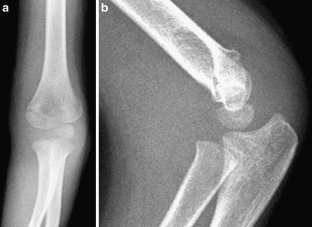

Fig. 3